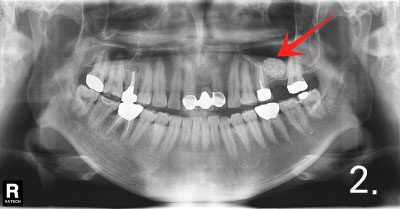

Case #3

This case is referred from other dental clinic to Dr. Jang due to sinusitis and implant failure. There is basically not enough bone to place implant.

After removal of failed implant and treatment for maxillary sinusitis, sinus bone graft was performed successfully

Implant placement and crown fabrication were completed without any complication